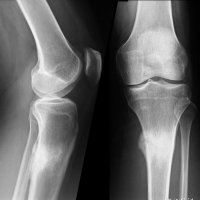

PATELLAR TENDON-LATERAL FEMORAL CONDYLE FRICTION SYNDROME

Patellar tendon-lateral femoral condyle friction syndrome, also known as Hoffa fat pad impingement syndrome, is a common cause of anterior knee pain in active individuals. It is thought to be due to patella maltracking or imbalance of the forces between medial and lateral vastus muscles causing impingement of the superolateral aspect of Hoffa fat pad between the inferior patella and the lateral femoral condyle.

Patients with Hoffa syndrome would present with acute or chronic sharp pain below the patella which is worsened by activities like walking, prolonged standing, wearing high heel shoes or any other activity that puts the knee into full extension. On examination, there may be swelling in the infrapatellar region, with point tenderness at the inferior pole of the patella.

The diagnosis is classically made with MRI and usually occult on radiography and CT. MRI findings include focal area of high T2 signal (edema) at the inferolateral aspect of the patellofemoral joint, within the superolateral portion of the infrapatellar fat pad. A cystic lesion can sometimes be found between the lateral femoral condyle and the lateral retinaculum. Associated findings include lateral patellar subluxation and patella alta (Insall-Salvati ratio greater than 1.2) which are found in around 90% of cases. Conservative treatment is usually successful, although full recovery may take time.